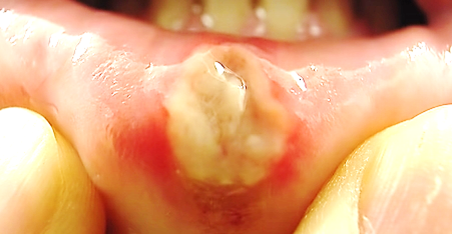

구내염은 사실 지금까지도 어떻게 생기는지 그 원인을 정확히 밝혀내지 못했습니다.

구내염이 자주 생기는 분들의 몇 가지 유발요인이 있을 뿐입니다.

이러한 요인을 잘 살펴서 구내염을 예방해보세요.